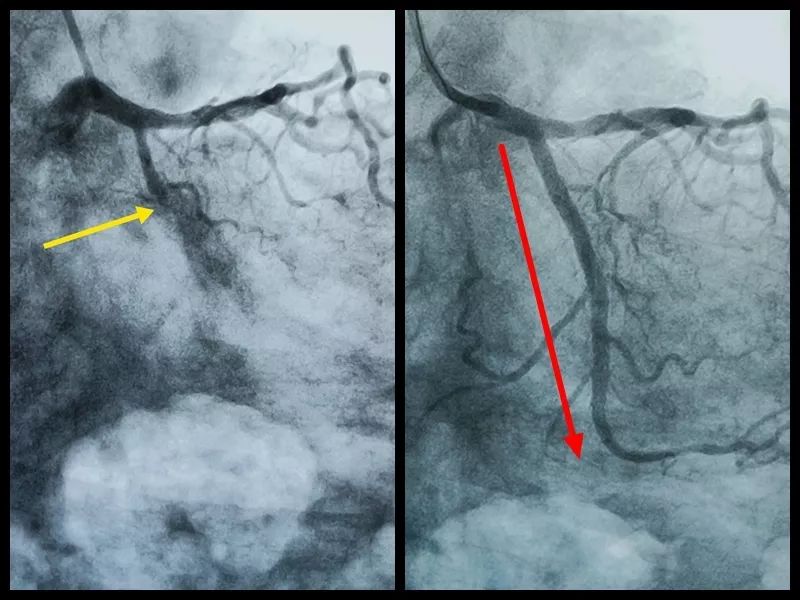

今天小编就在北京胸科医院心脏中心手术室遇到一个,中年男性,近期觉得憋喘,难受。上台造影发现,回旋支100%闭塞,也就是我们说的完全堵死,不过血了。

从造影可以看出来,患者的回旋支在箭头这个位置向下,看不见了。

这就是做完支架之后前后的对比。是不是看着很过瘾?